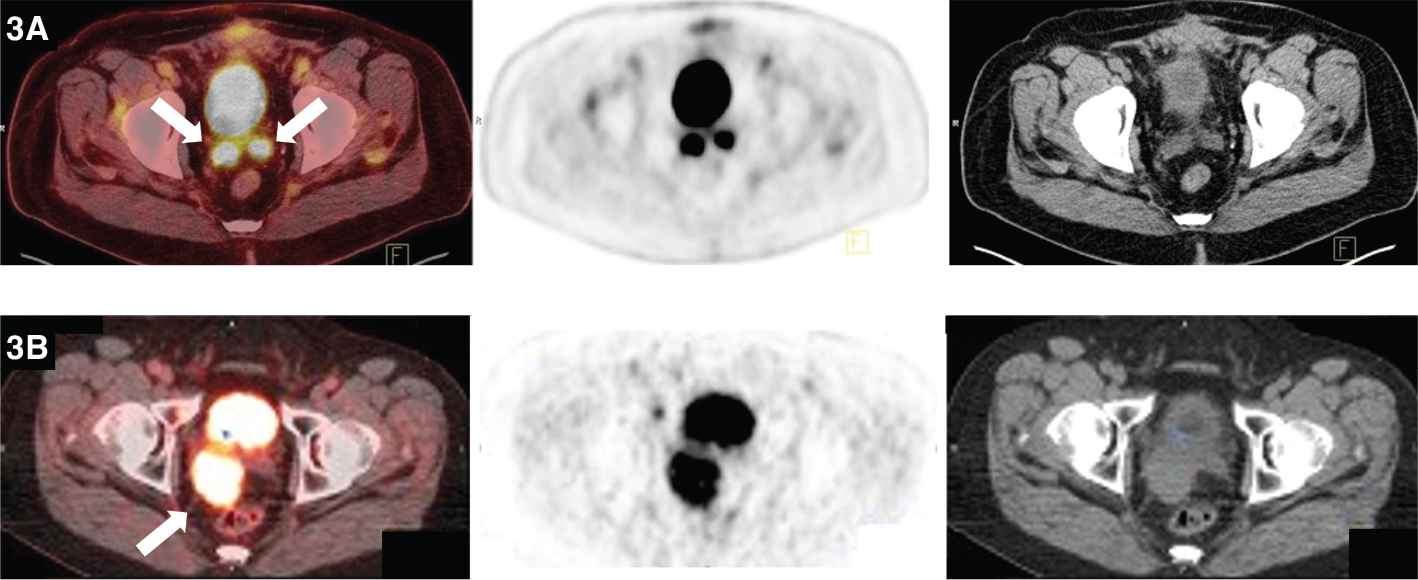

Fig 5

Figure 5. Pulmonary nodules. FDG PET/CT demonstrates hypermetabolic activity within two right lung pulmonary nodules. This patient was status post left testicular mass resection revealing a nonseminomatous germ cell tumor with pathologic staging of pT4 Nx Mx. Findings on PET/CT were consistent with pulmonary metastases resulting in final staging of T4 N0 M1.

Ultrasound, with approximately 100% sensitivity, is generally the main modality used for diagnosis. Ultrasound can differentiate intra- versus extratesticular involvement and whether the lesion is cystic or solid. Magnetic resonance imaging (MRI) plays a secondary role. The role of FDG-PET/CT in the evaluation of testicular cancer has been controversial. After surgery, CT is the main modality for follow-up. PET/CT of the primary tumor is rarely used. Shao et. al. demonstrated that PET/CT could differentiate between benign and malignant testicular masses with a sensitivity of approximately 90% and specificity of approximately 80% (22, 23, 25). Carcinoma in-situ is thought to be a precursor of germ cell cancers. The utility of PET/CT at this stage is yet to be defined as normal testicular activity on F-18-FDG scans is very variable. Cook et. al. determined FDG PET/CT to be useful in the setting of equivocal primary staging CT scans, in ruling out active disease in the setting of residual masses after chemotherapy, and in locating active sites of disease in the setting of rising tumor markers and a negative CT scan (29). For seminomas PET/CT staging has been reported to have a sensitivity of 92% and a specificity of 84% when compared to standard staging models. For non-seminomas, the sensitivity was lower at 77%. PET/CT resulted in a change in management in a quarter of cases (29 out of 121 cases) (23, 30). PET/CT is advantageous in evaluating post-chemotherapy residual retroperitoneal lymph nodes. Seminoma patients with a residual nodal mass exceeding 3 cm can represent a serious challenge. FDG PET/CT is recommended by the European Association of Urology (EAU) in evaluation of residual masses after seminoma excision. FDG-PET/CT proved to be superior to standard imaging in predicting viable tumors. A negative predictive value of 94% was determined when evaluating lesions >3 cm. EAU does not have a recommendation for use of PET/CT in non-seminomas (29, 31).